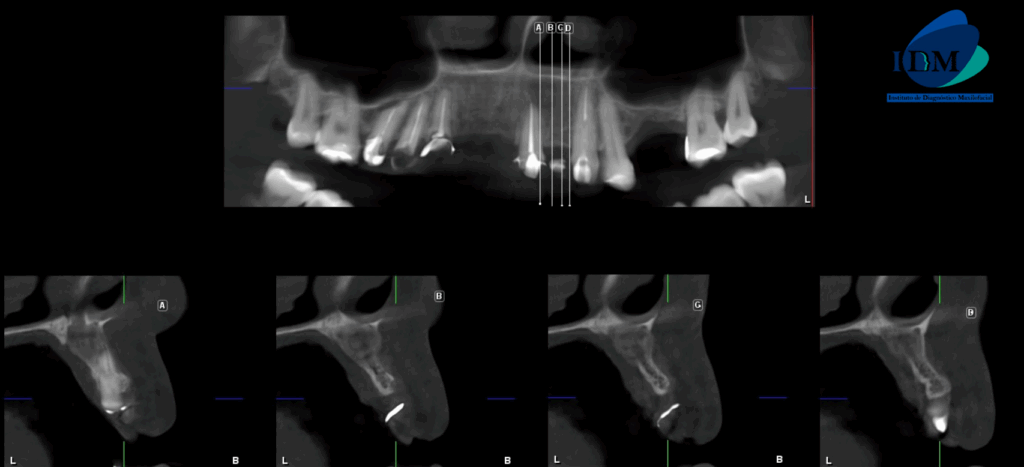

A la evaluación de la tomografía volumétrica (CBCT) en los cortes axiales (Figura 2) y transaxiales (Figura 3), se aprecia imagen mixta localizada a nivel apical de pieza 21, de limites definidos, que se extiende en sentido cefálico caudal desde piso de fosa nasal izquierda hasta apical de pieza 21, en sentido mesio distal desde cortical de conducto nasopalatino hasta nivel de zona de pieza 22, ocasionando adelgazamiento y expansión de tabla ósea vestibular y palatina, adelgazamiento del piso de fosa nasal izquierda, borramiento parcial de cortical de conducto nasopalatino.

CORTES AXIALES

CORTES TRANSAXIALES